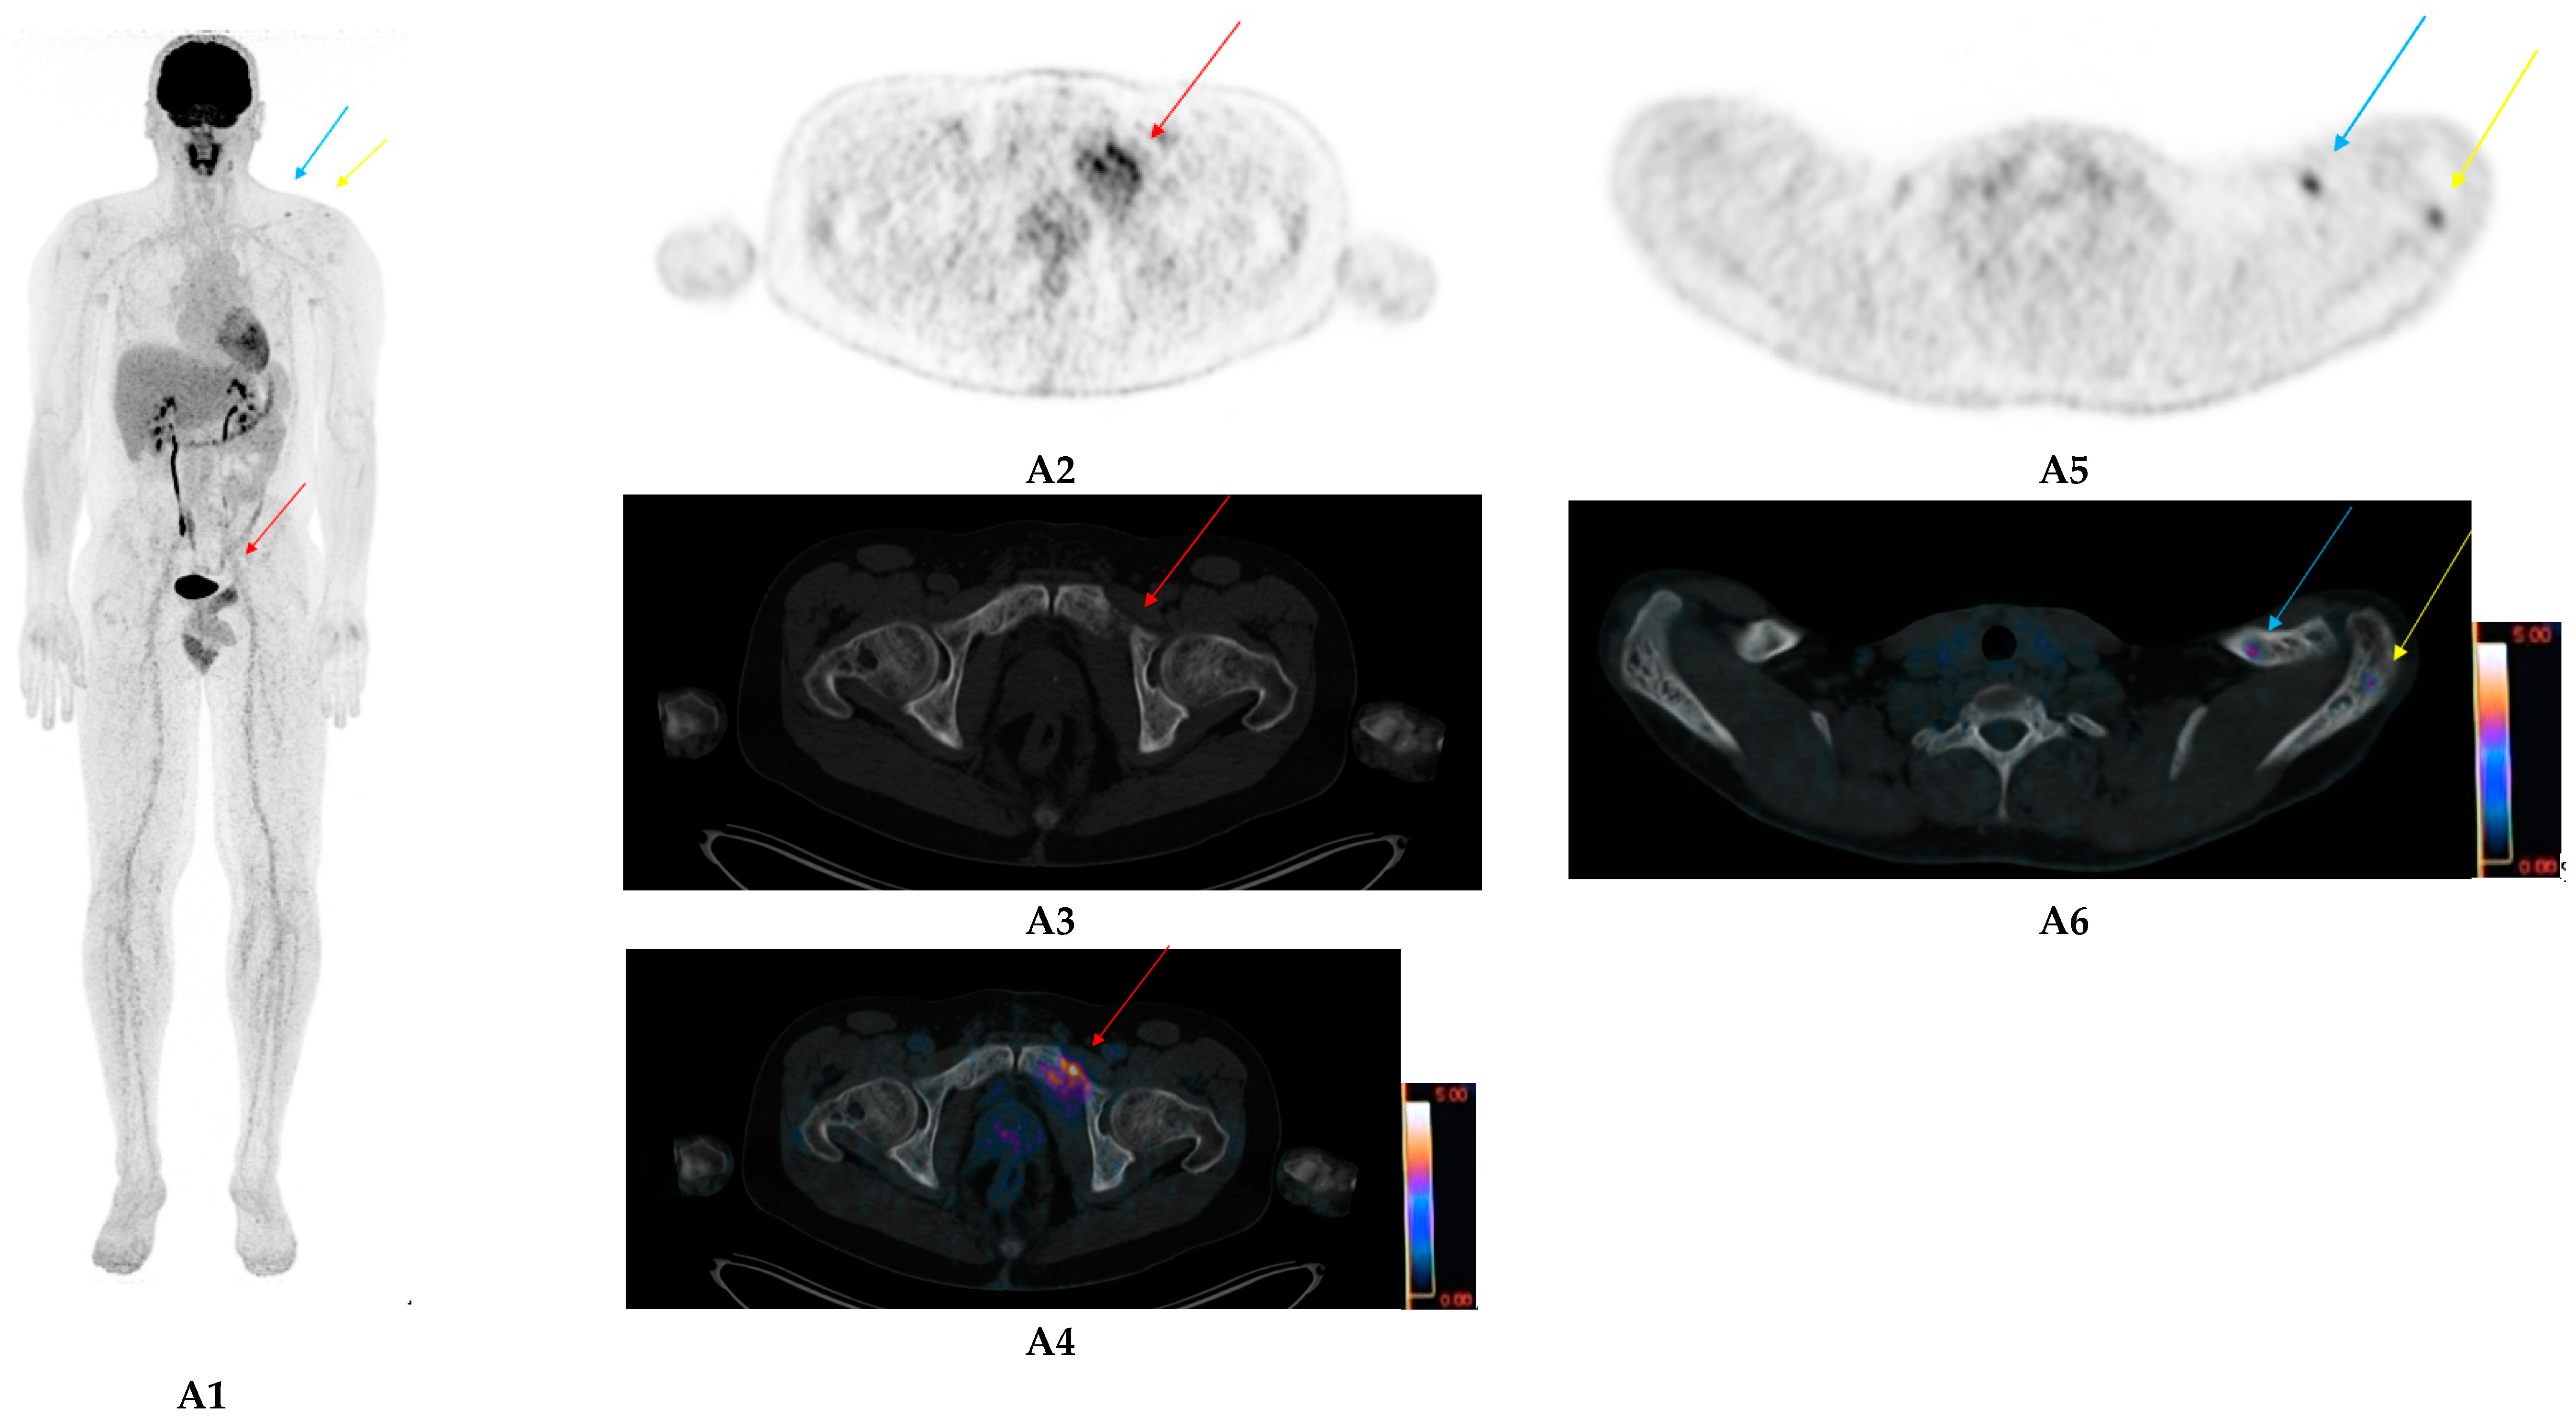

- Pan, Q.; Cao, X.; Luo, Y.; Li, J.; Feng, J.; Li, F. Chemokine receptor-4 targeted PET/CT with 68Ga-Pentixafor in assessment of newly diagnosed multiple myeloma: Comparison to 18F-FDG PET/CT. Eur. J. Nucl. Med. Mol. Imaging 2019, 47, 537–546. [Google Scholar] [CrossRef]